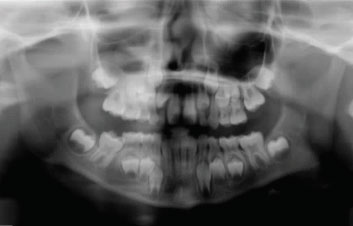

Figure 1—Panoramic radiograph

Figure 2—Bitewing radiograph taken using a DEXIS digital x-ray sensor, demonstrating a large carious lesion on a mandibular left first primary molar with no evidence of inter-radicular pathology